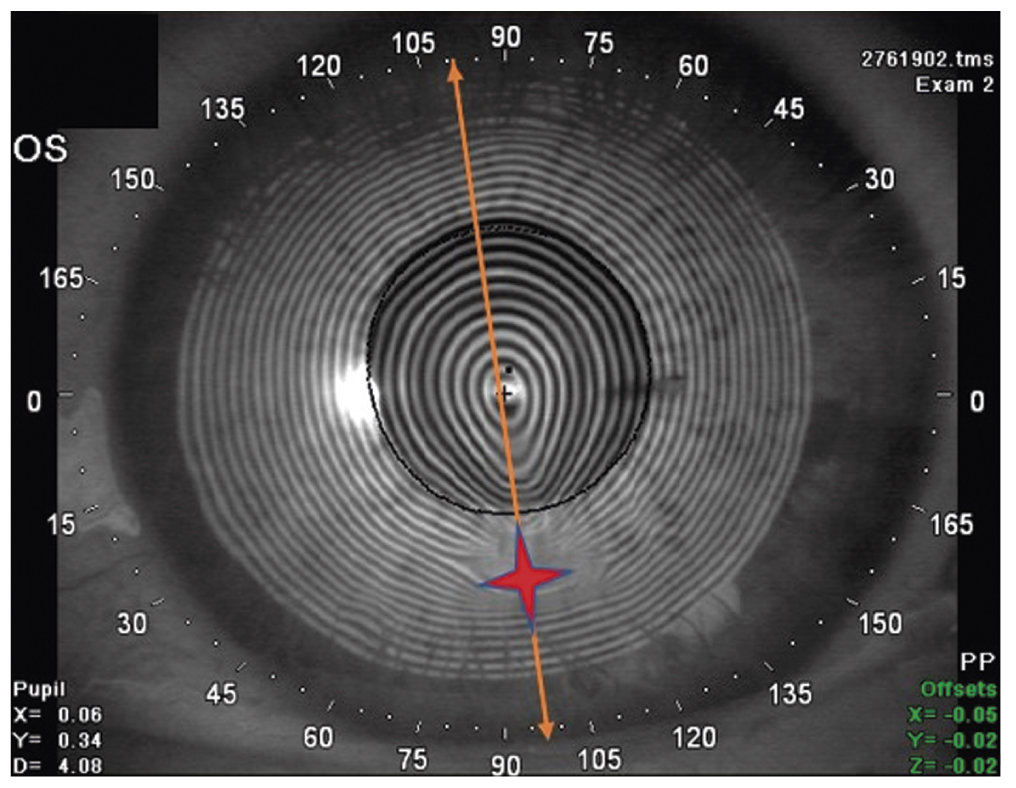

Рис. 2. Кератоскопическая карта левого глаза пациента М.: зона максимальной кератэктазии (разошедшийся кератотомический рубец) отмечена красной звёздочкой, ось самого плоского меридиана — жёлтой стрелкой

Fig. 2. Keratoscopic map of the left eye of patient M. Red asterisk: the zone of maximum keratectasia (divergent tangential scar); yellow arrow: the axis of the flattest meridian

Динамика и исходы. Пациенту запланировали ультразвуковую факоэмульсификацию катаракты обоих глаз с имплантацией торических ИОЛ. Для расчёта оптической силы ИОЛ кератометрические показатели определяли на проекционном кератотопографе TMS-4 (Tomey, Япония). Ни лазерный интерферометр IOL Master 700 (Carl Zeiss, Германия), ни диагностическая проекционная система Verion (Alcon, США) не позволили измерить величину преломляющей силы роговицы ввиду её выраженной деформации из-за посткератотомической кератэктазии и иррегулярного астигматизма. Кератотопограф TMS-4 выявил наиболее плоский меридиан роговицы (зона максимальной кератэктазии), по отношению к которому ось планируемого к имплантации цилиндра торической ИОЛ повёрнута на 90 градусов (рис. 1, 2). Для расчёта оптической силы ИОЛ правого глаза использовали показатели 25,39 D ax 50 и 32,70 ax 140 (рис. 3), для левого глаза — 28,49 D ax 98 и 38,40 ax 8 (рис. 4).

Трудности торической имплантации связаны в первую очередь с получением правильных метрических параметров для расчёта оптической силы ИОЛ из-за иррегулярности и высоких степеней астигматизма с неопределёнными главными меридианами. В представленных случаях кератометрические показатели получили на кератотопографе, работа которого основана на проекции на роговицу колец Плачидо. Кератоскопические карты позволяют определить зону кератэктазии в виде максимального расхождения и каплевидной деформации (вытянутости) колец Плачидо в направлении положения наиболее уплощённого меридиана. Графическое представление формы роговицы облегчает хирургу выбор оси имплантации торической ИОЛ, в том числе с применением интраоперационной кератоскопии.